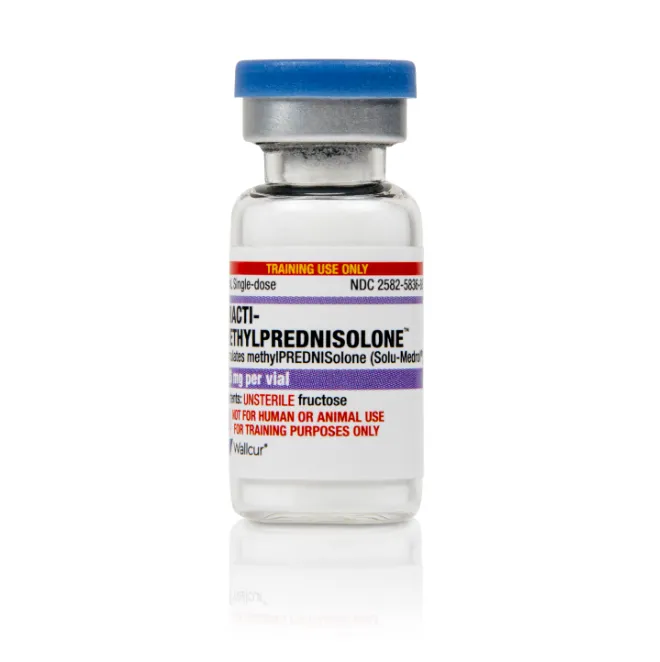

Vai pulsar com metilprednisolona? Confira os cuidados essenciais antes de iniciar a pulsoterapia: Um checklist rápido e prático para garantir segurança na prescrição!

Luís Sette

12 meses atrás